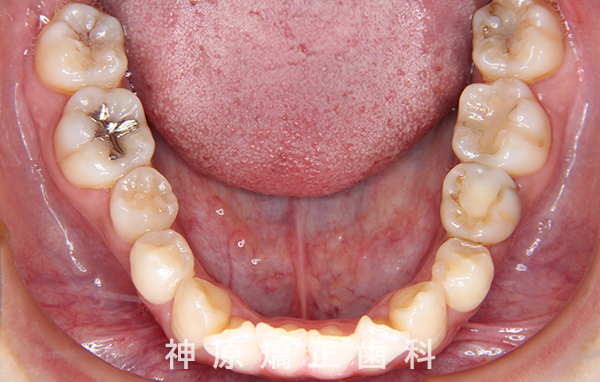

下顎:舌側矯正装置 - 抜歯 / 非抜歯

- 上顎左右第一小臼歯、

下顎右側第二小臼歯、下顎左側第二乳臼歯

今回の矯正治療にあたり、矯正精密検査の結果をもとに診断を行いました。その結果、左下の永久歯が生まれつき欠損していました。歯並びの乱れや口元の突出感を改善するため、小臼歯と残っている乳歯を抜くことが必要だと判断しました。